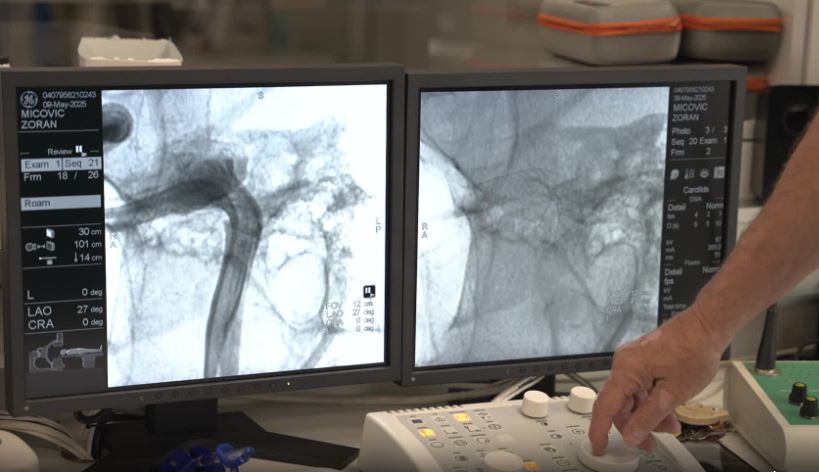

Zoran Mićović iz Tivta prvi je pacijent kojem je u Crnoj Gori urađena intervencija interkranialne aneurizme u budnom stanju. Taj zahvat izveden je u Kliničko bolničkom centru Berane, a pacijent se samo par minuta kasnije osjećao dobro.

Intervenciju je radio dr Slobodan Ćulafić, svjetski priznati interventni neuroradiolog.